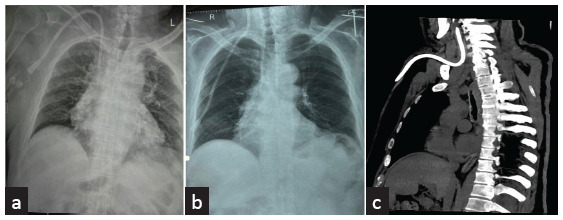

Spontaneous Intravascular Cephalad Migration of Tunneled Cuffed Catheter - An Unusual Late Complication and Role of Re-Imaging.